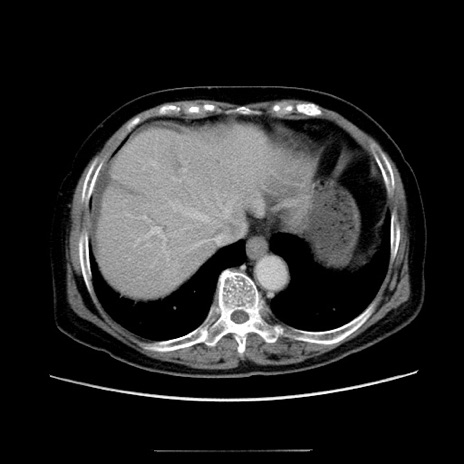

症例5(横断像)

【症例】70歳代女性

【主訴】お腹が張る

【現病歴】1週間くらい前から腹部膨満の自覚あり。昨日夜から増悪したため、本日救急外来受診。

【身体所見】意識清明、BT 36.5℃、BP 165/106mmHg、HR 80bpm、SpO2 98%、腹部:膨満、軟、自発痛・圧痛なし、触診にて不快感あり、腸蠕動音:減弱

【データ】WBC 12600、CRP 1.04